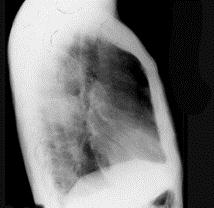

问题 72岁,男,呼吸急促、气喘4个月,请结合胸片和CT,选出最可能的诊断 ( )

选项 A、韦格肉芽肿 B、支气管腺瘤 C、错构瘤 D、肺结核 E、肺癌

答案 E